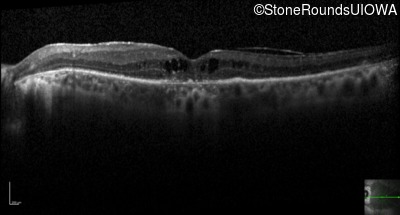

Optical Coherence Tomography - Right - 20/50 -1

Exemplar / OCT Stack